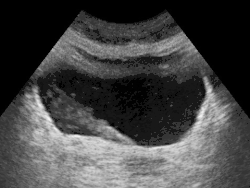

Ultrassonografia mostrando um jato de urina entrando na bexiga (grande seção preta) através do ureter.

Os ureteres são um componente do sistema urinário. A urina, produzida pelos rins, viaja ao longo dos ureteres até a bexiga. Ele faz isso por meio de contrações regulares chamadas peristaltismo.[2]